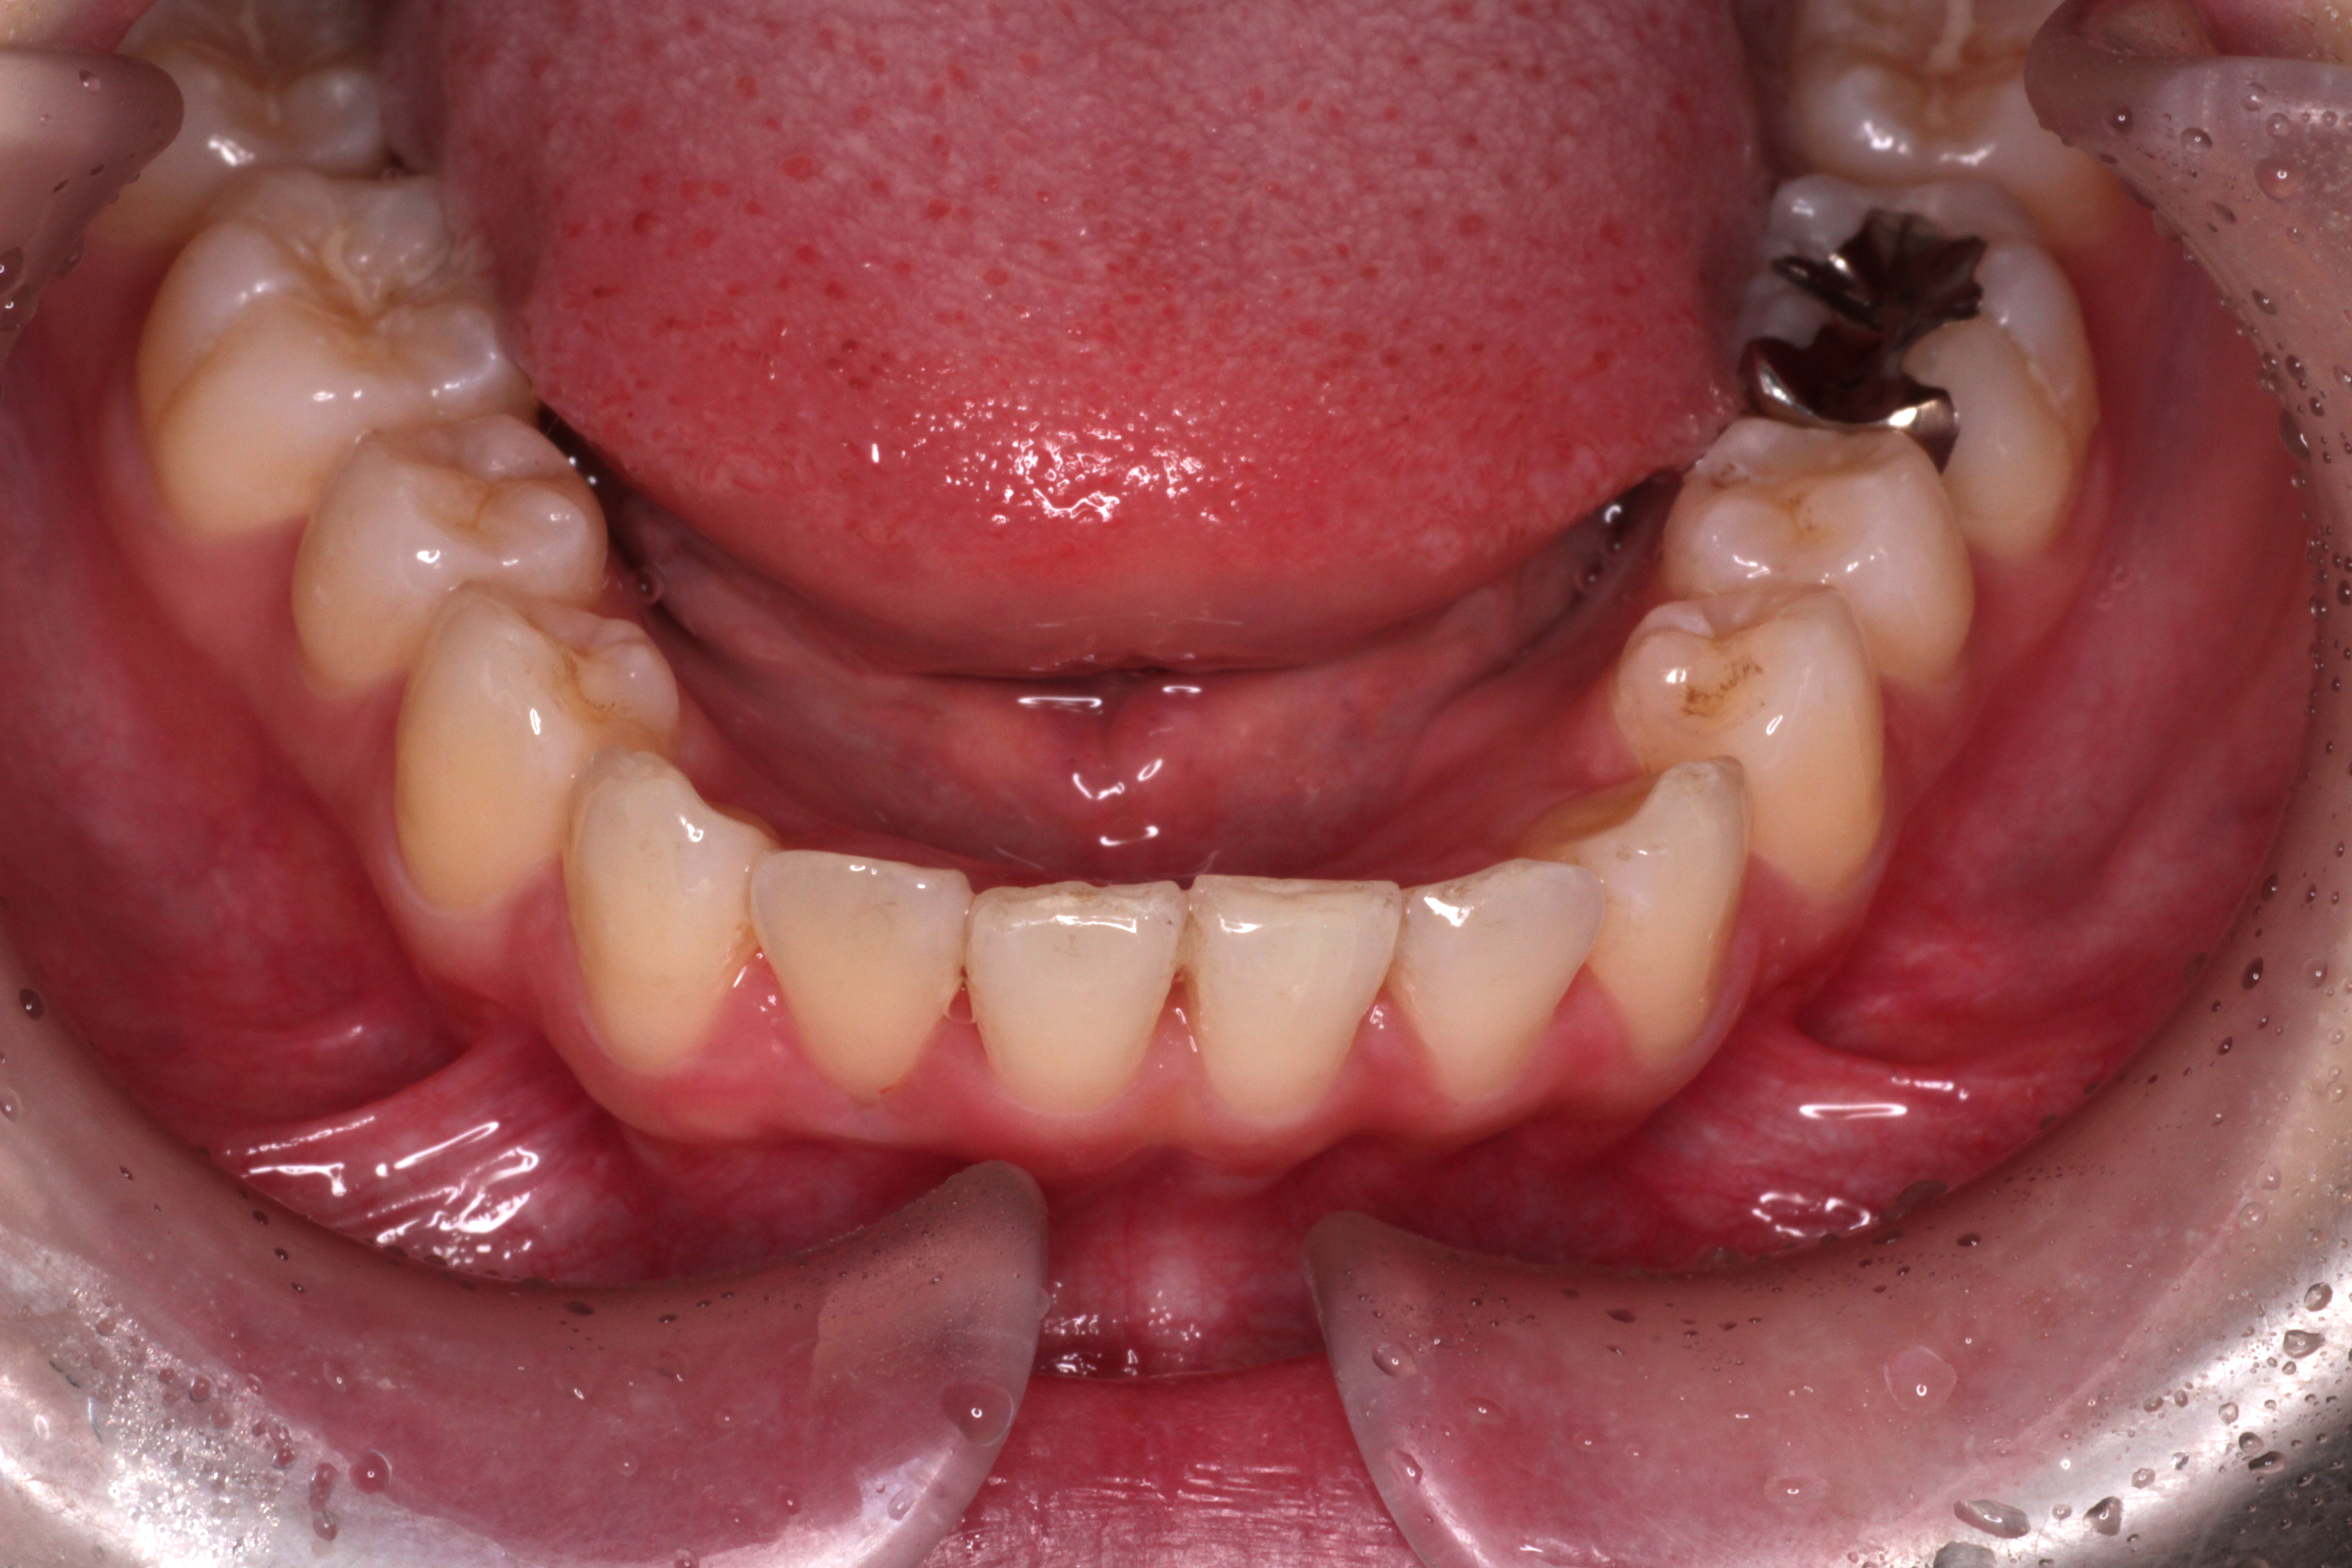

↓お口の中の状態です。

⑴深かった咬み合わせがしっかりと改善されました。

⑵右下の2番目の歯のずれも治りました。

⑶右上の2番目の歯の咬み合わせがよくなりました。

⑷正中も綺麗に合いました。

これで気になるところが改善されたので矯正は終了です。